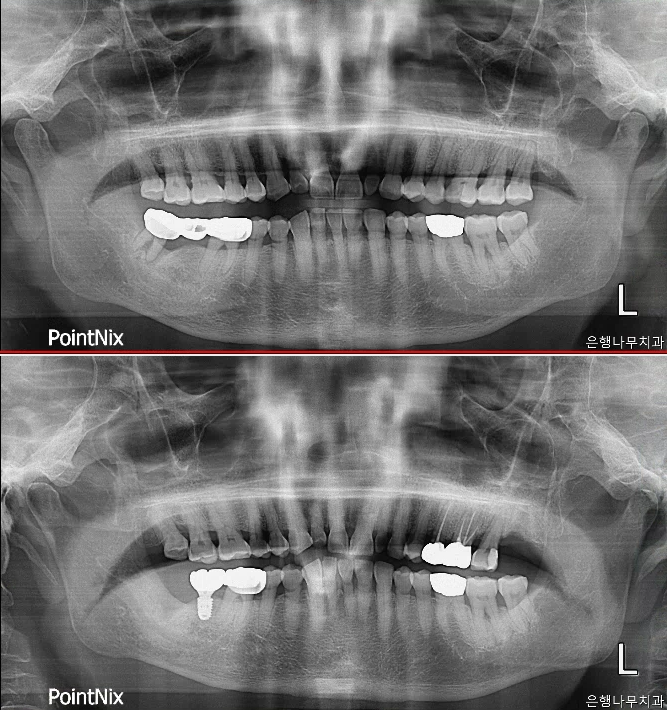

은행나무치과의원

은행나무치과의원은 2020년에 문을 연 따끈따끈한 새 치과라요. 가족을 진료하는 맘으로 최선을 다하겠다는 굳은 의지가 돋보이는 곳이라 카네. 실옥동, 북부 온천동에서 젤 가까운 치과를 목표로, 늘 환자 곁을 지키겠다는 포부를 밝히고 있구먼. 임플란트, 신경치료, 사랑니 발치, 스케일링, 충치 치료 등 다양한 진료를 하고, 처방전은 미소지움 101동 맞은편 온약국에서 받을 수 있다 하니 참고하이소.

2020년 1월에 개원한 곳으로, 깔끔하고 쾌적한 환경에서 진료받을 수 있는 것이 장점이라요. 환자들에게 늘 최선을 다하는 모습을 보여주어 믿음이 가는 곳이며, 특히 임플란트와 신경치료, 사랑니 발치에 대한 만족도가 높은 편이라 카네. 과잉 진료 없이 꼭 필요한 치료만 하는 곳으로 입소문이 자자하다는 점도 알아두면 좋겠지라?